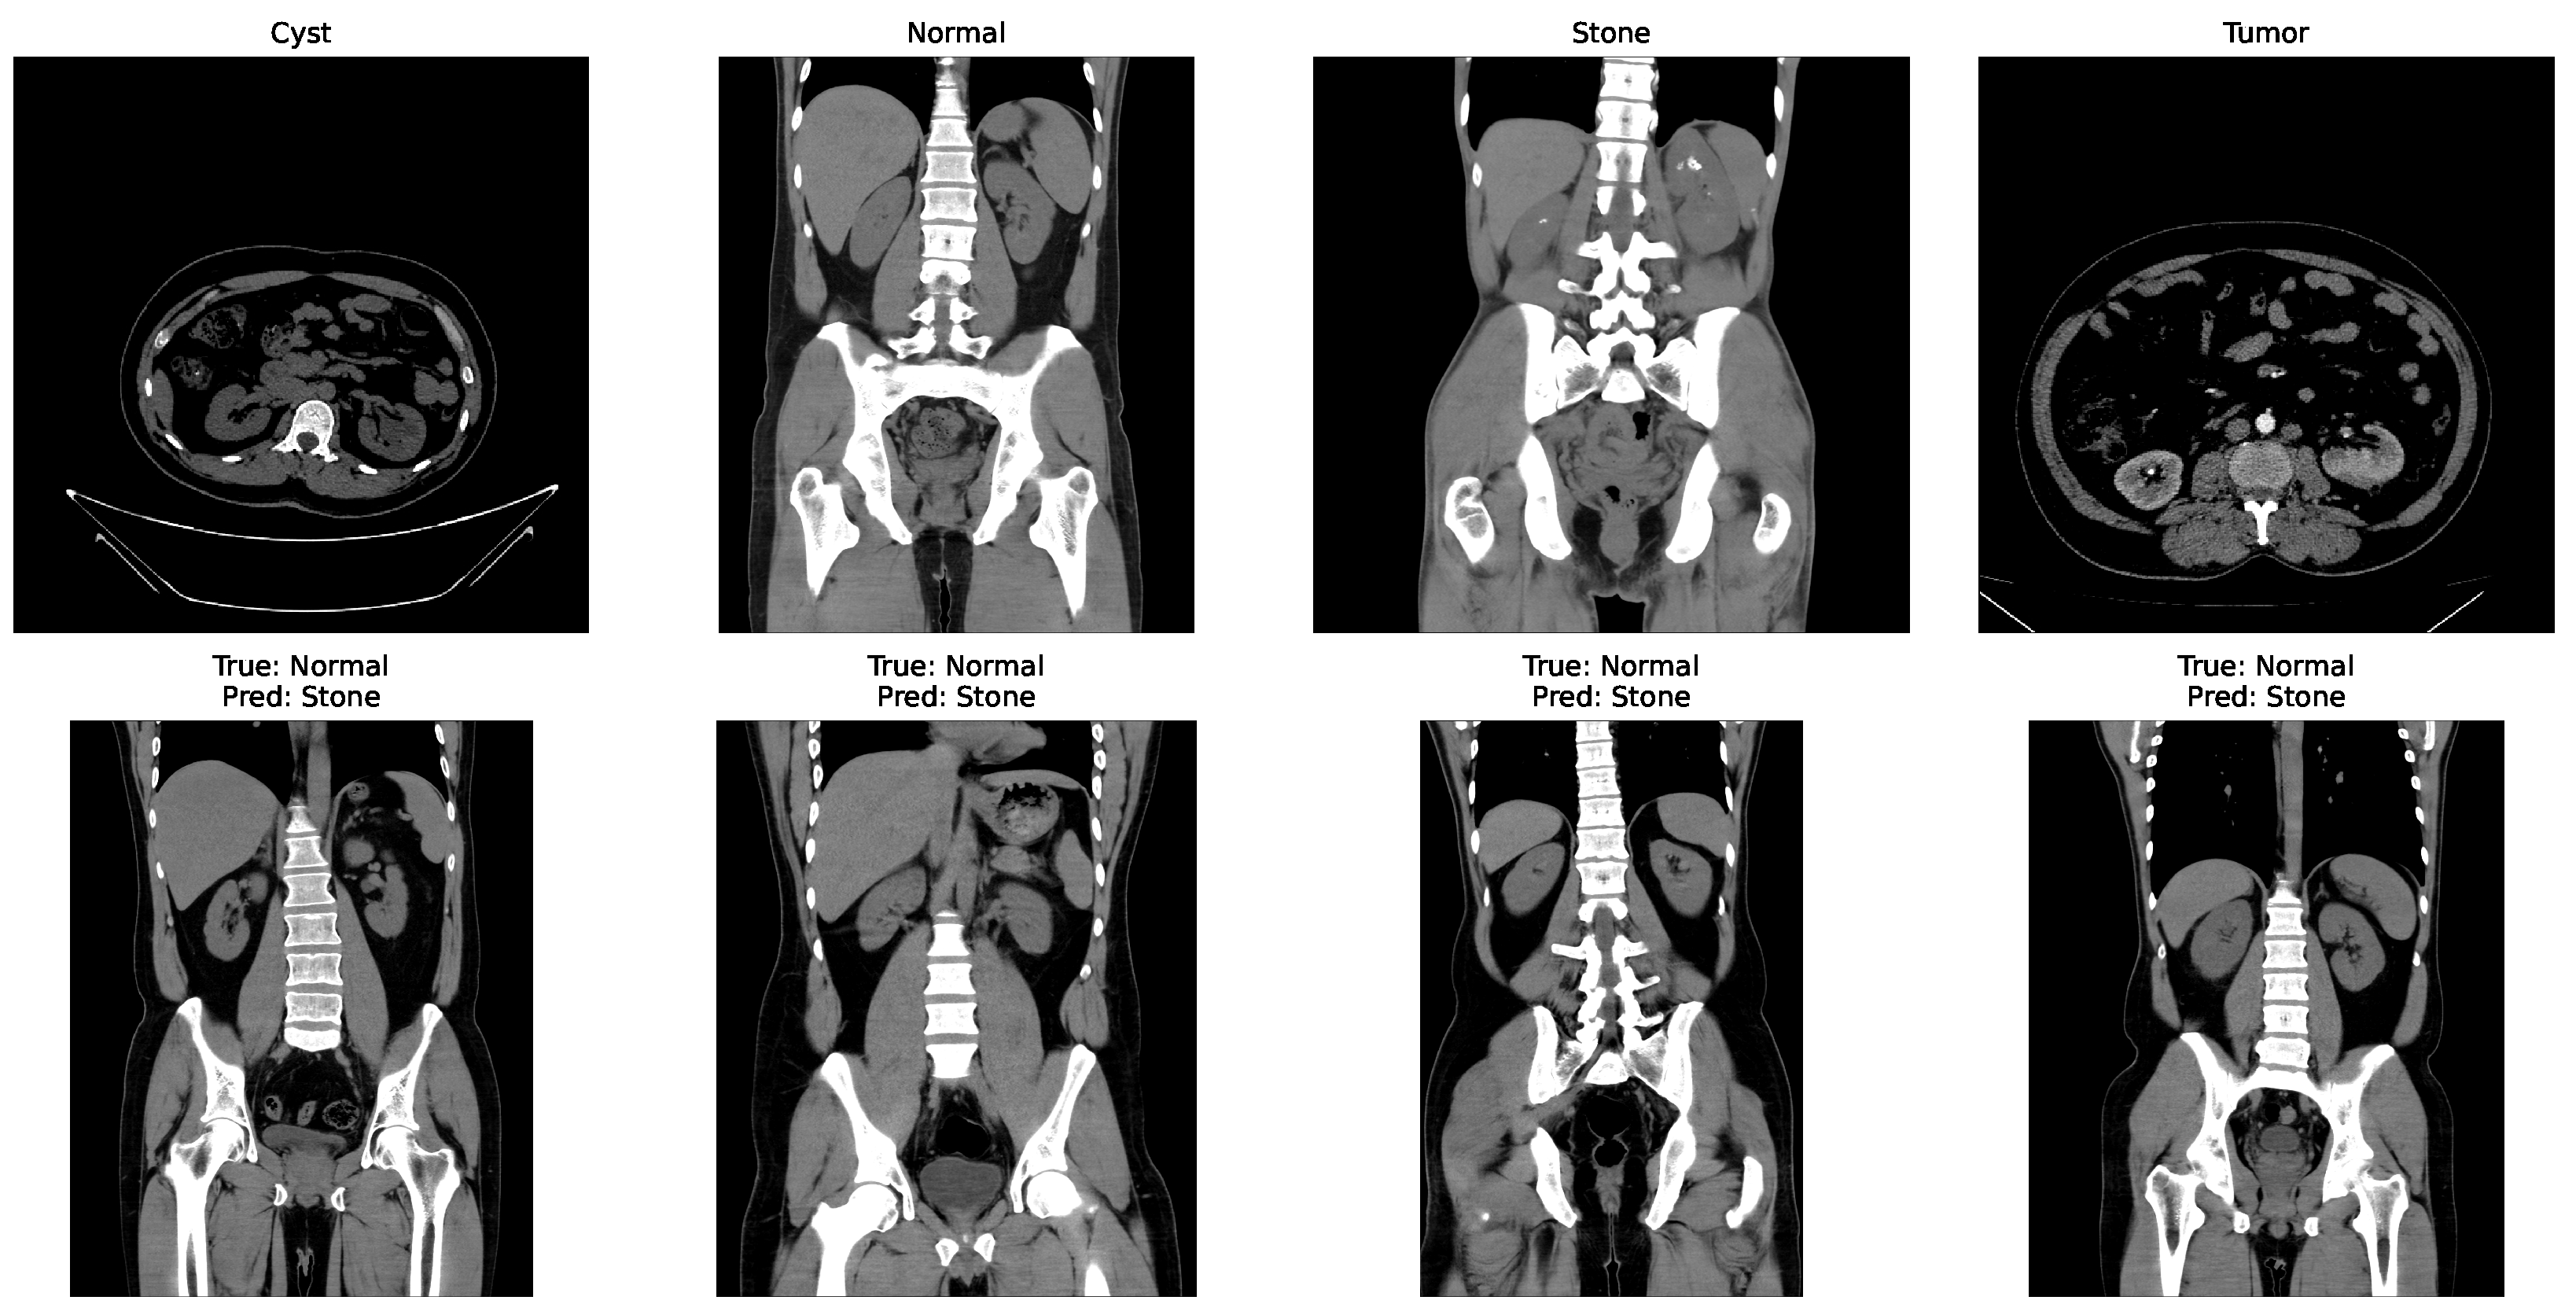

In the matrix, the diagonal elements represent correctly classified instances, and the rest of the elements indicate misclassifications. The incorrectly classified numbers are 18, 18, and 21 for baseline, Dataset A, and Dataset B, respectively. Although the model performs consistently well across all datasets, a slightly higher misclassification rate is observed in the stone class. This is mainly attributed to the smaller sample size of the stone category, which limits the model’s ability to learn its feature variability, even after applying SMOTE balancing. Additionally, the visual inspection of misclassified cases shown in Figure 9 revealed that some stone images share overlapping visual characteristics with cyst and tumor classes, such as low-contrast textures and irregular boundaries, making them challenging to distinguish even for deep learning models.

Figure 9.

Some incorrectly classified images.